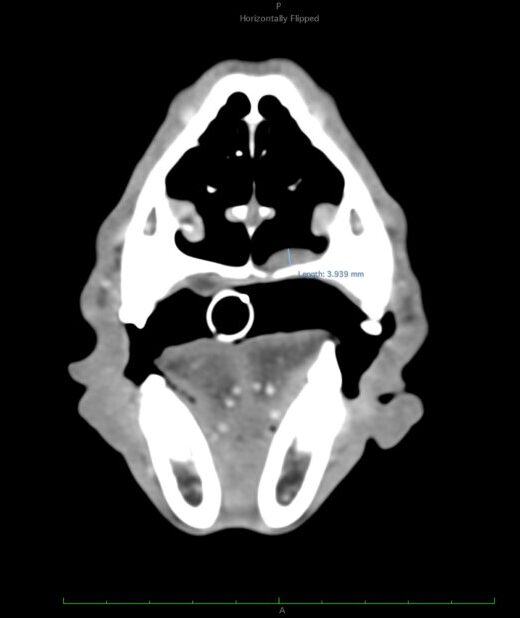

Las constantes vitales del paciente son compatibles con la normalidad. En la exploración de la cavidad oral se detecta una lesión de aproximadamente 3 cm de diámetro que se origina en la mucosa del paladar duro. No presenta linfadenomegalia submandibular o cervical palpable.

Dos semanas más tarde se realiza el TC de reestadiaje y se detecta la presencia de enfermedad metastásica en pulmón. Adicionalmente, la afectación completa del paladar y la invasión en cavidad nasal hacen que se descarte la cirugía como terapia local.

A los 18 meses del diagnóstico, los cuidadores refieren la aparición de hifema y exoftalmia en el ojo derecho, lo que sugiere metástasis, además de una masa perianal compatible con neoplasia indiferenciada (posible melanoma amelanótico). En el estudio de TC se documenta una respuesta completa de la lesión primaria y metástasis nodales y una remisión casi completa de las metástasis pulmonares (lesiones milimétricas equívocas) (imagen 1). Se realiza la resección de la masa perianal, pero los cuidadores rechazan la enucleación.

A los 28 meses se realiza un TC de re-estadiaje antes de considerar el segundo protocolo de radioterapia, donde se documenta una progresión objetiva de la masa oral y ligera progresión de la metástasis pulmonar (imagen 1).